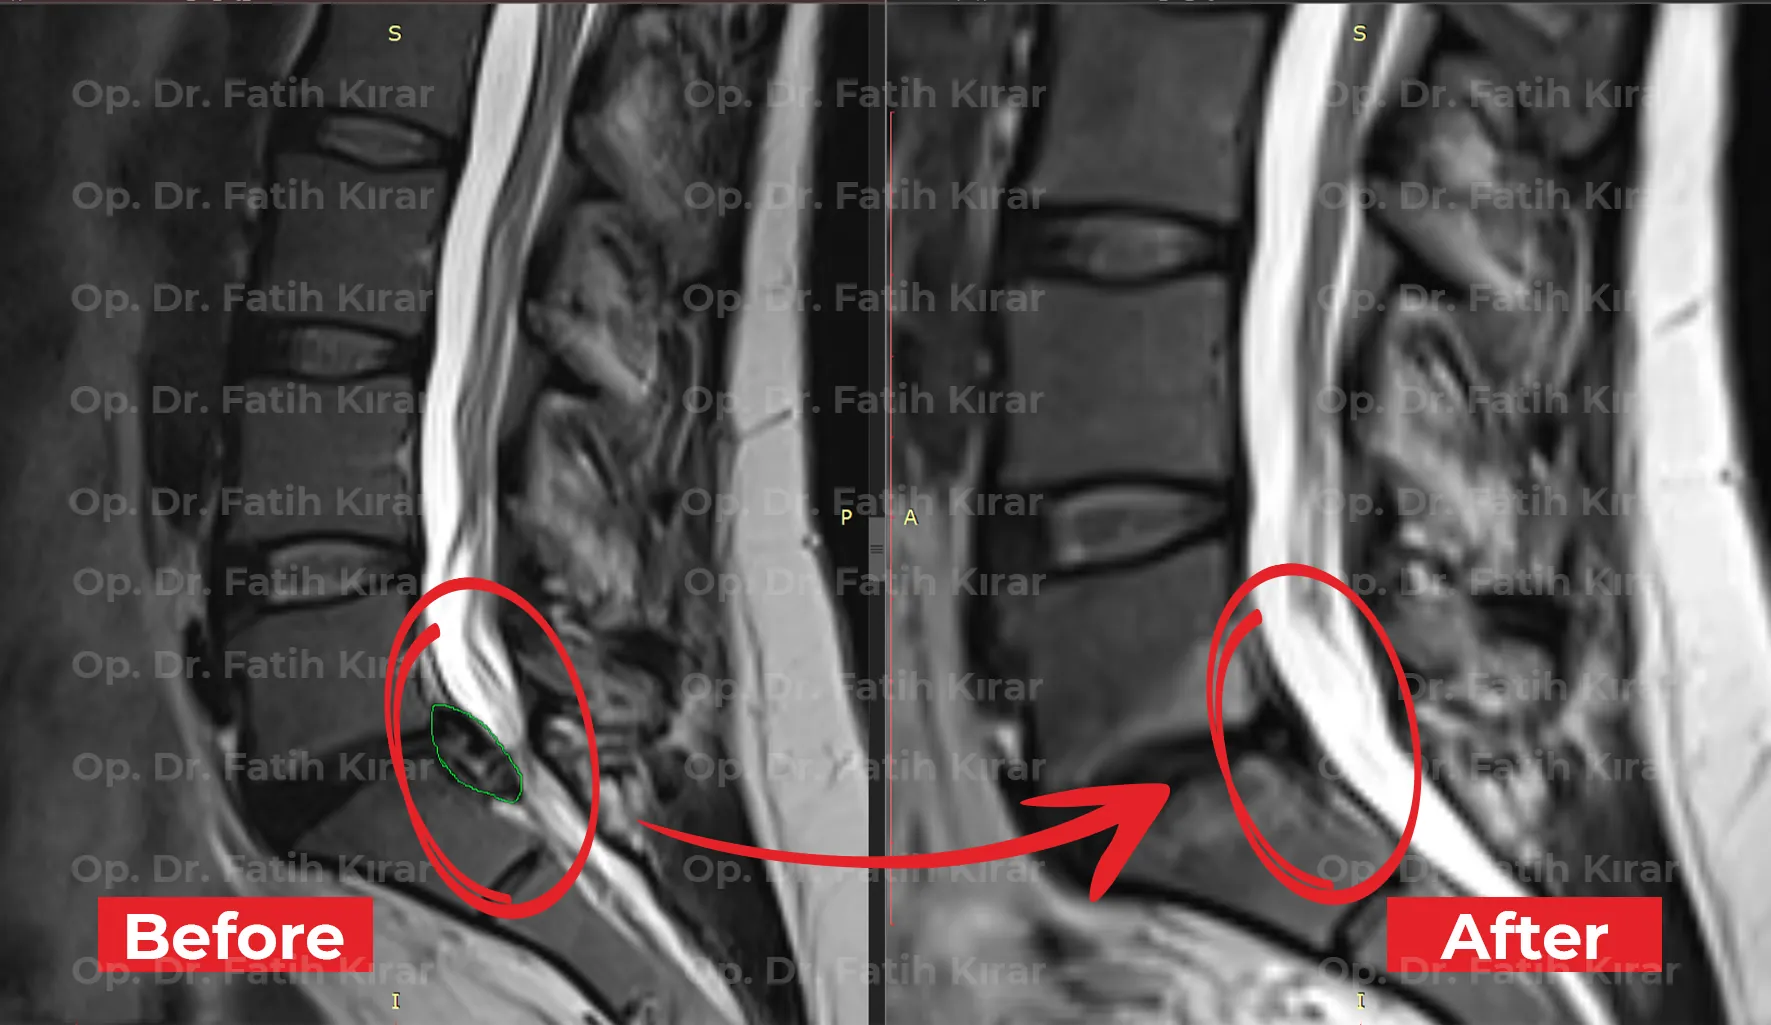

Clinical Results

MRI Images

Before and after treatment MRI images of our real patients